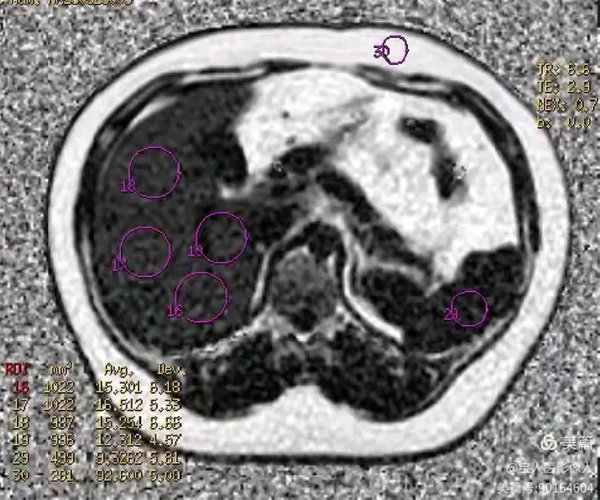

图6

PDFF测值,测量全肝实质多部位的脂肪分数值12%—17%,提示:脂肪肝,MR-PDFF,二级,中度。